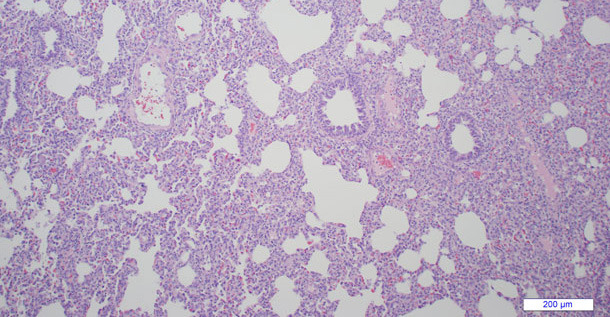

Les signes cliniques, (voir ci-dessus) accompagnés de lésions macroscopiques évidentes et l’historique clinique font souvent suspecter le SDRP, particulièrement dans les épisodes aigus. Les lésions microscopiques caractéristiques dans les poumons ou d’autres tissus (figure 2) sont aussi évocatrices de lésions de SDRP mais non pathognomoniques. Tout diagnostic clinique provisoire doit être confirmé par la détection de SDRPv (c’est-à-dire du virus, des antigènes viraux et/ou du matériel génomique viral) sur les porcs atteints en utilisant des méthodes de laboratoire, conjointement avec les lésions typiques. L’immunohistochimie est beaucoup utilisée dans les tissus conservés dans du formol pour détecter la présence de l’antigène viral à l’intérieur des lésions, cependant, la PCR est la principale technique de laboratoire pour détecter la présence du SDRPv sur une large variété de prélèvements cliniques. La sérologie fournit une mise en évidence indirecte de l’infection ou de l’exposition au SDRPv mais ne détermine pas si la maladie est causée par le virus. Le double prélèvement d’échantillons de sang sur un intervalle de 2 à 3 semaines peut être utile pour déterminer si l’infection par le SDRPv est en relation avec le problème clinique. Une série de prélèvements de sang aux différents stades de production peut être utile pour déterminer l’âge auquel les animaux sont généralement infectés par le SDRPv dans un élevage.

La découverte la plus courante dans la maladie respiratoire due au SDRP est la lésion pulmonaire interstitielle mais sa répartition peut varier, de multifocale à lobulaire ou diffuse. Macroscopiquement, les poumons des porcs touchés présentent des tâches foncées qui varient dans leur extension (figure 1). Les ganglions sont généralement gonflés, foncés et œdémateux ou kystiques. Microscopiquement, on observe une pneumonie interstitielle non suppurative (figure 2). De plus, chez les porcs atteints, on peut observer de la myocardite, de la rhinite et/ou de l’encéphalite non suppurative légère sur les porcs atteints. Chez les truies avec une infection aigue de SDRP on a observé des lésions dans le placenta, de l’endométrite et de la myométrite On n’observe généralement pas de lésions sur la plupart des fœtus avortés et des mort-nés atteints seulement de SDRP. S’ils en ont, on a observé les suivantes :

Figure 2 : Microphotographie de pneumonie interstitielle sur un poumon atteint par le SDRPv. Les sept alvéoles sont dilatées et l’espace interstitiel est rempli de plusieurs cellules inflammatoires..

(Photo aimablement fournie par Dr. Greg Stevenson de la Iowa State University)